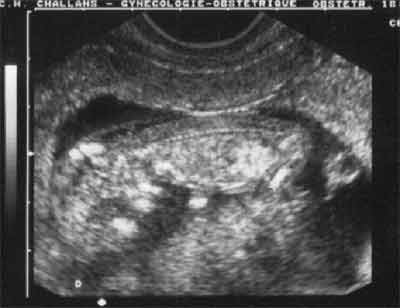

Coupe longitudinale